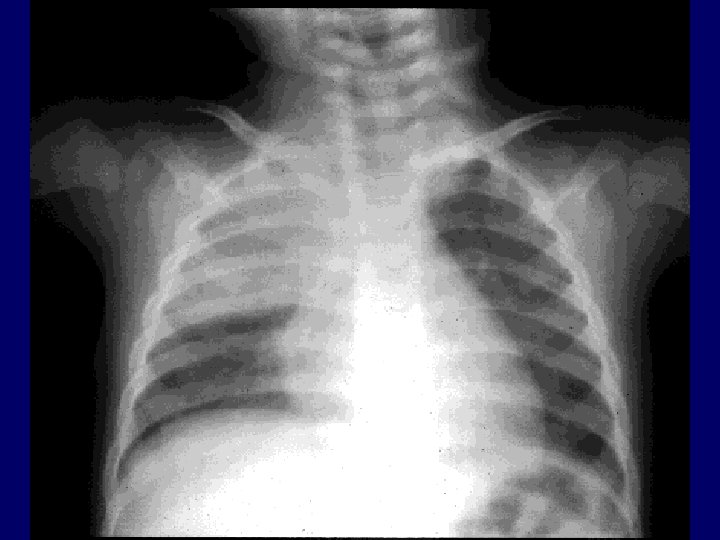

Инструментальные исследования • Рентгенография грудной клетки. Позже 10 -12 часа - инфильтративные тени. • Общий анализ крови. Лейкоцитоз, сдвиг формулы влево, токсическая зернистость нейтрофилов, редколейкемоидная реакция (неблагоприятный прогноз), увеличение СОЭ. • Мокрота – окраска мазка по Граму, культуральное исследование • Функция внешнего дыхания - нарушение характеристик свидетельствует о тяжести состояния, рестриктивных нарушениях. • Исследование газов крови